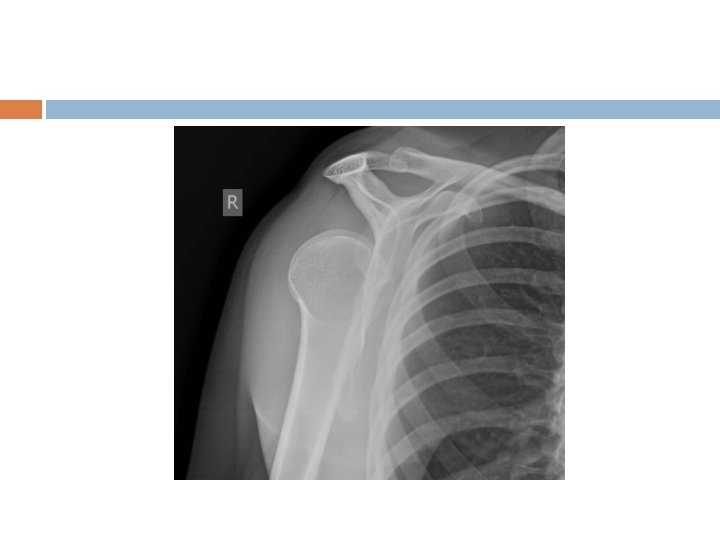

Acromioclavicular Joint AC Sprain/Separation- trauma (acute or repetitive) causing damage/tearing of acromioclavicular and coracoclavicular ligaments Tenderness over AC joint; possibly elevation of clavicle on palpation Classification: -Type I: sprain of AC ligament (CC intact) -Type II: tear of AC (CC intact); slight elevation of clavicle on xray -Type III: complete tear of AC and CC ligs and elevation of clavicle -Types IV-VI: keeps getting worse and damage to surrounding structures

AC Separation

Grade 3

AC Sprain History- fall on shoulder or on outstretched arm (hockey player checked into boards or FB player landing on shoulder; cyclist falling off bike) Exam- cross arm test and O’Brien’s if localizes to AC joint Treatment- sling, ice, analgesics for Type I, II and usually III (sometimes III needs surgery); IV-VI need surgery Recovery- 1 to 6 weeks (or keep playing…)